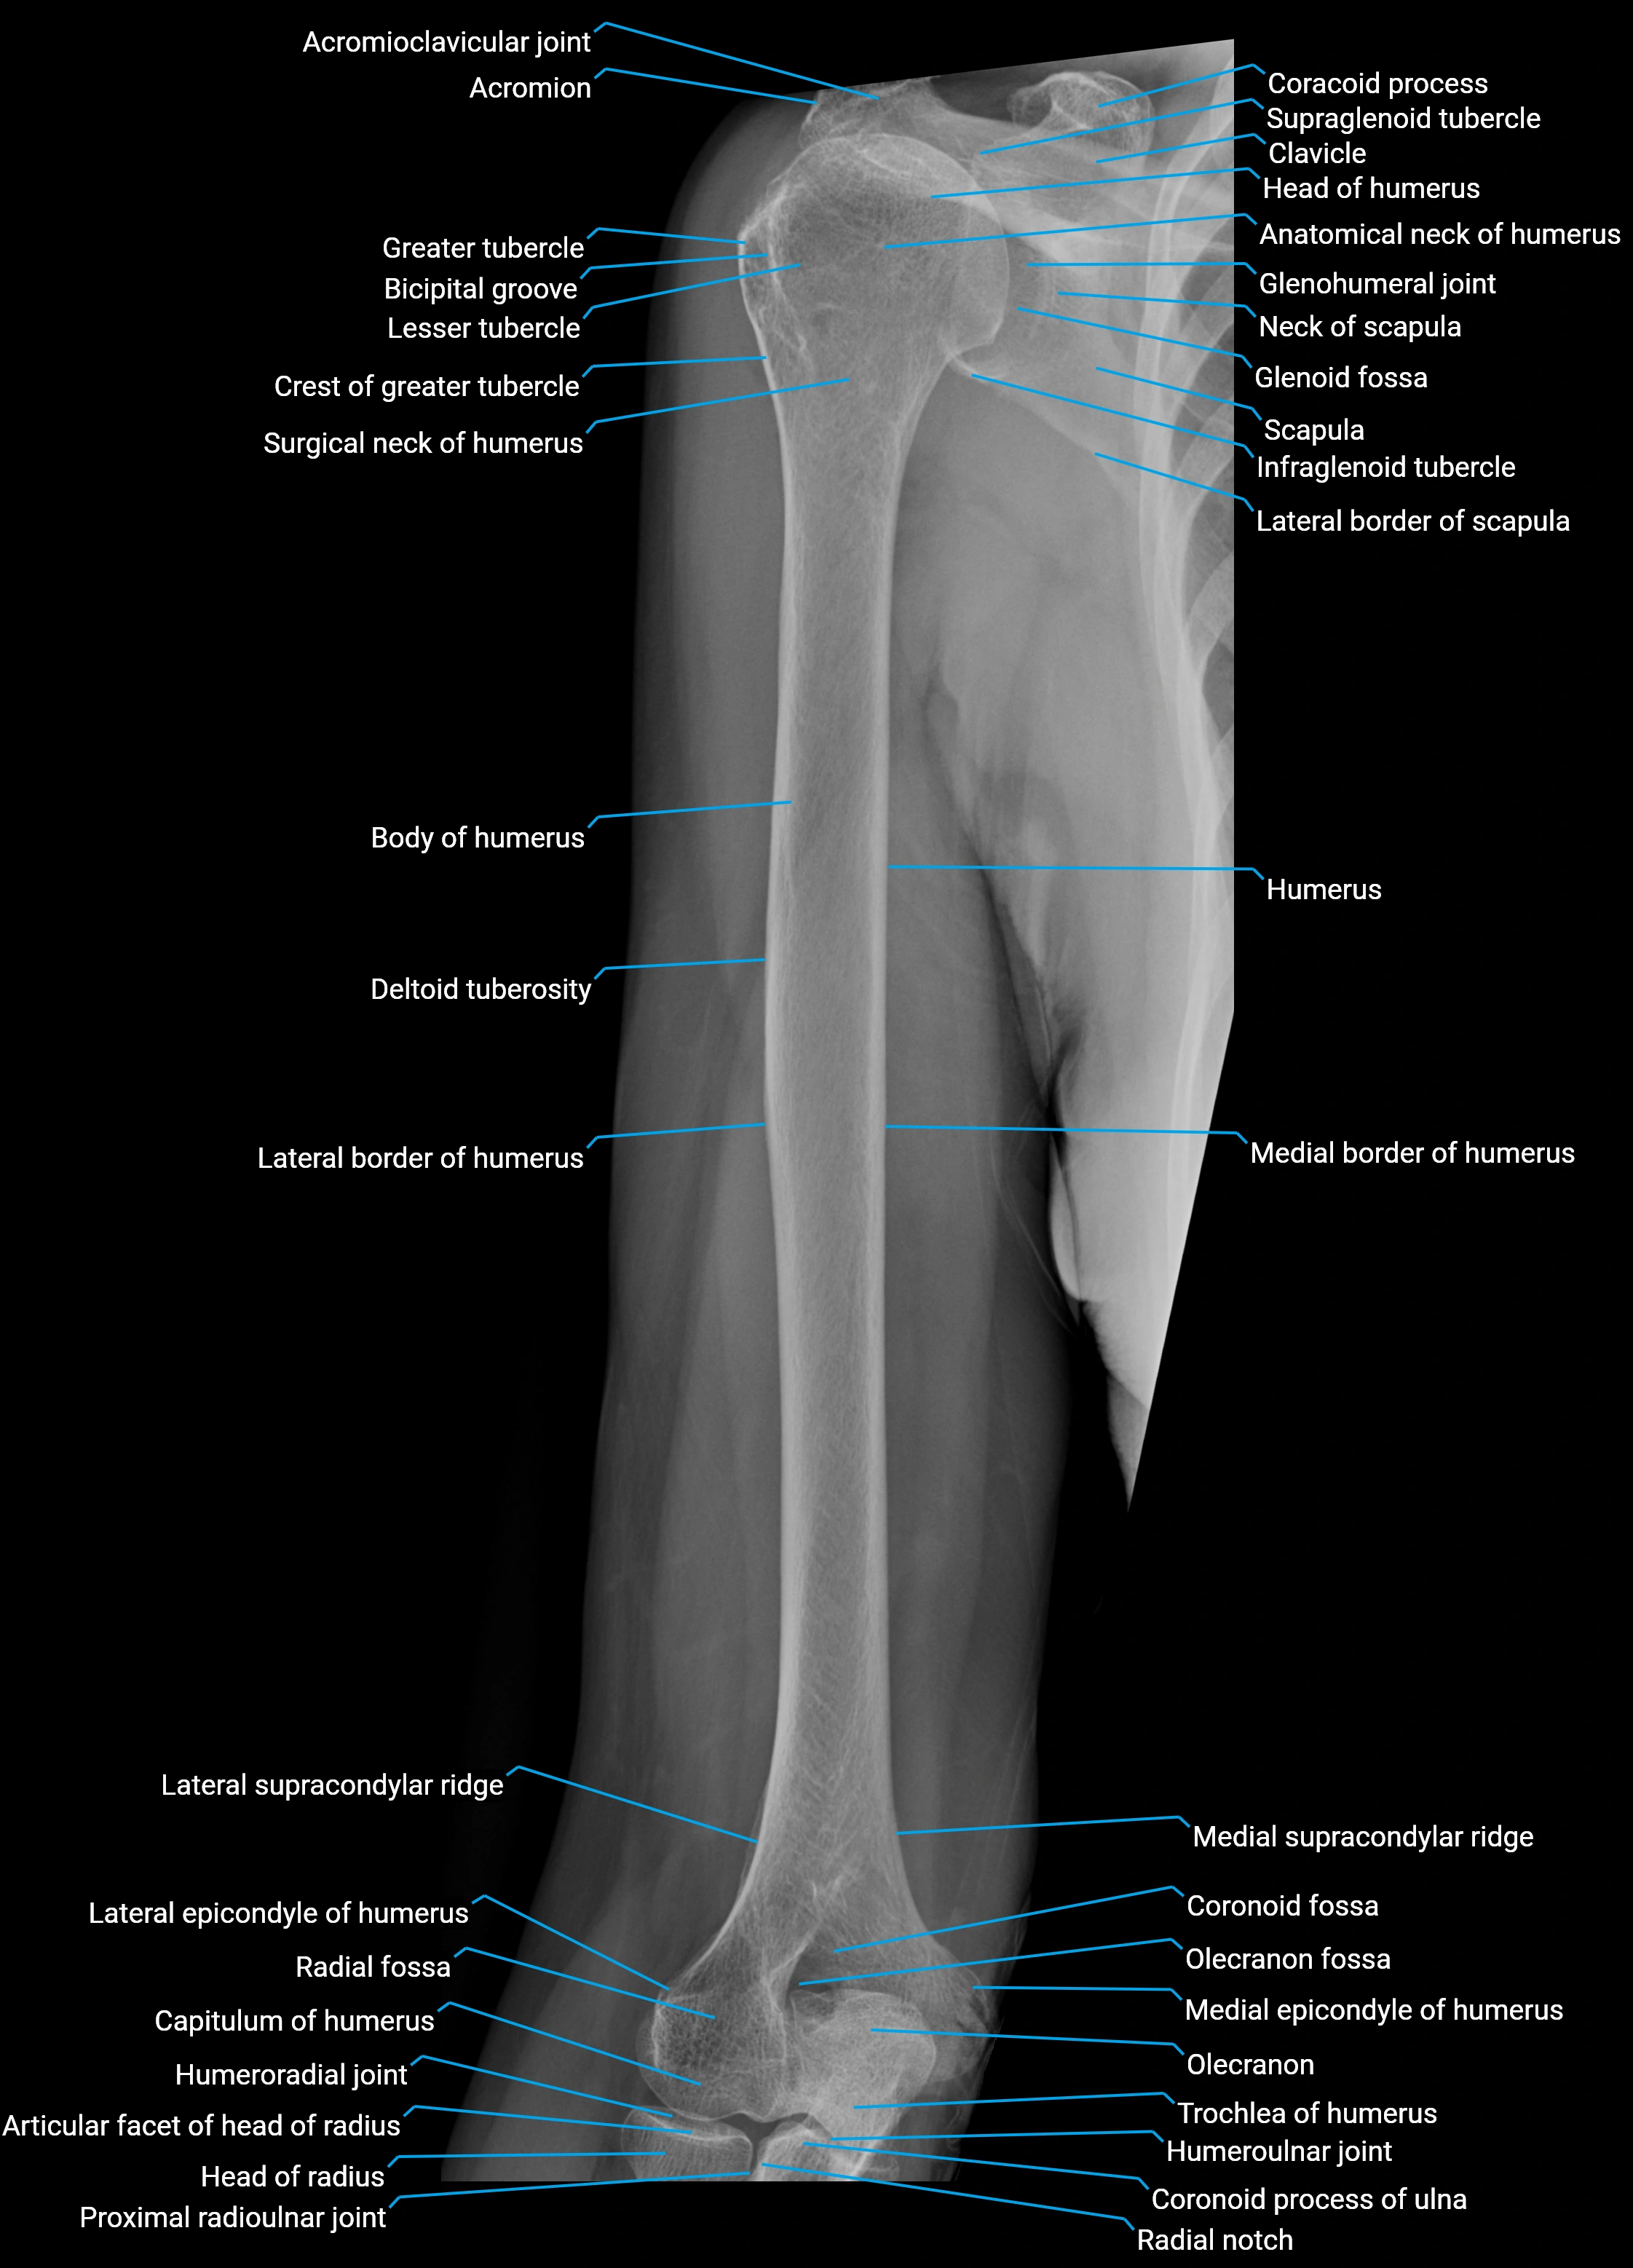

The acromial part of the deltoid muscle (also known as the middle or lateral part) forms the thick, lateral aspect of the deltoid, giving the shoulder its characteristic rounded contour. It arises from the lateral border and superior surface of the acromion process of the scapula and inserts into the deltoid tuberosity of the humerus.

Origin, Course, and Insertion

• Origin: Lateral border and superior surface of the acromion process of the scapula

• Course: Fibers run vertically downward over the lateral aspect of the shoulder

• Insertion: Deltoid tuberosity on the lateral surface of the humerus, via a thick tendinous attachment